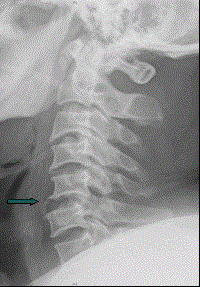

患者男,38岁,车祸伤后导致颈部疼痛、四肢瘫痪,排尿、粪失禁,ASIA分级C级,入院时间为伤后6 h,佩戴颈托入院。于急诊行颈椎正侧位X线片(如图)。...

问题 患者男,38岁,车祸伤后导致颈部疼痛、四肢瘫痪,排尿、粪失禁,ASIA分级C级,入院时间为伤后6 h,佩戴颈托入院。于急诊行颈椎正侧位X线片(如图)。 此患者应给予的进一步处理是(提示 血钠2.8 mmol/L,血钾3.0 mmol/L,经补充0.9%氯化钠溶液后无明显变化。)